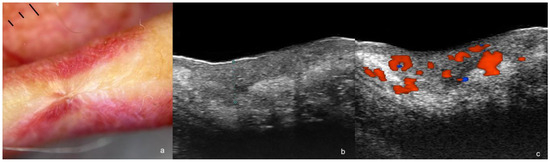

1.4. Bowen Disease

1.5. Post-Operative Recurrence or Remnant SCC